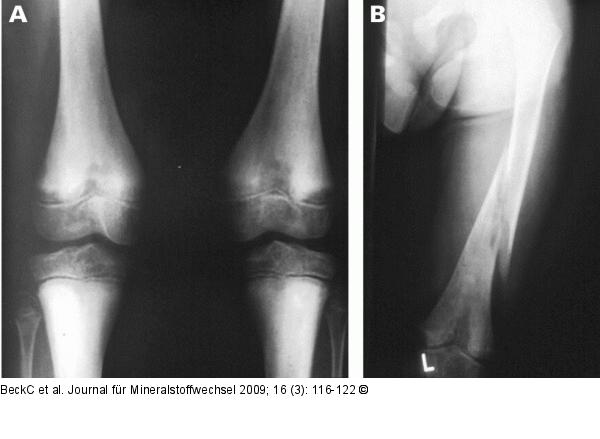

Abbildung 2a-b: Hypophosphatasie Konventionell radiologische Diagnostik. Röntgenbild A zeigte ein a. p.- Röntgenbild beider Kniegelenke. HP-typisch ist die inhomogene Knochenstruktur mit hypomineralisierten (Looser-Zonen) und kompensatorisch hypermineralisierten Regionen. Bild B zeigt eine Femurfraktur nach Bagatelltrauma bei insgesamt inhomogener Knochenstruktur und pathologischer Mineralisation des distalen Femurs. |

Abbildung 2a-b: Hypophosphatasie

Konventionell radiologische Diagnostik. Röntgenbild A zeigte ein a. p.- Röntgenbild beider Kniegelenke. HP-typisch ist die inhomogene Knochenstruktur mit hypomineralisierten (Looser-Zonen) und kompensatorisch hypermineralisierten Regionen. Bild B zeigt eine Femurfraktur nach Bagatelltrauma bei insgesamt inhomogener Knochenstruktur und pathologischer Mineralisation des distalen Femurs. |